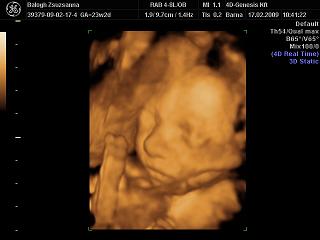

4D: előtte 3az egyben kávé+kóla+csoki. Muszáj volt, mert Adél drága csak délután kezd el mocorogni általában… De bevált, izgett- mozgott a drága!

Jajj

Magdi, nagyon be fog nektek is jönni, már olyan szépen látszik a kis arca, a vonásai!

Tiszta apja a kiscsaj, párom jól el is érzékenyült hogy ennyire hasonlít rá!

És jópár mosolygós kép készült róla: párom akkor simizte a hasam...

Adél